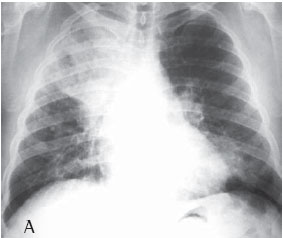

Quanto à classificação radiológica das grandes opacidades na radiografia de tórax verificou-se que: 23 pacientes apresentaram grande opacidade do tipo A (30,7%), 25 do tipo B (33,3%) e 27 do tipo C (36%) (Figuras 1A e 1B). Dos casos analisados, 74 apresentaram massas conglomeradas bilaterais, e apenas 1 apresentou lesão unilateral (Figuras 2A e 2B).

De todos os casos analisados (n = 75), apenas um apresentou grande opacidade unilateral simulando massa tumoral, sendo o diagnóstico de silicose feito através de toracotomia com biópsia pulmonar a céu aberto. Lesões solitárias de FMP são freqüentemente confundidas com câncer de pulmão. Considerando-se a maior incidência de câncer de pulmão nesses pacientes, é importante fazer uma abordagem diagnóstica para efetivamente diferenciar as lesões malignas das lesões benignas pneumoconióticas.(19)